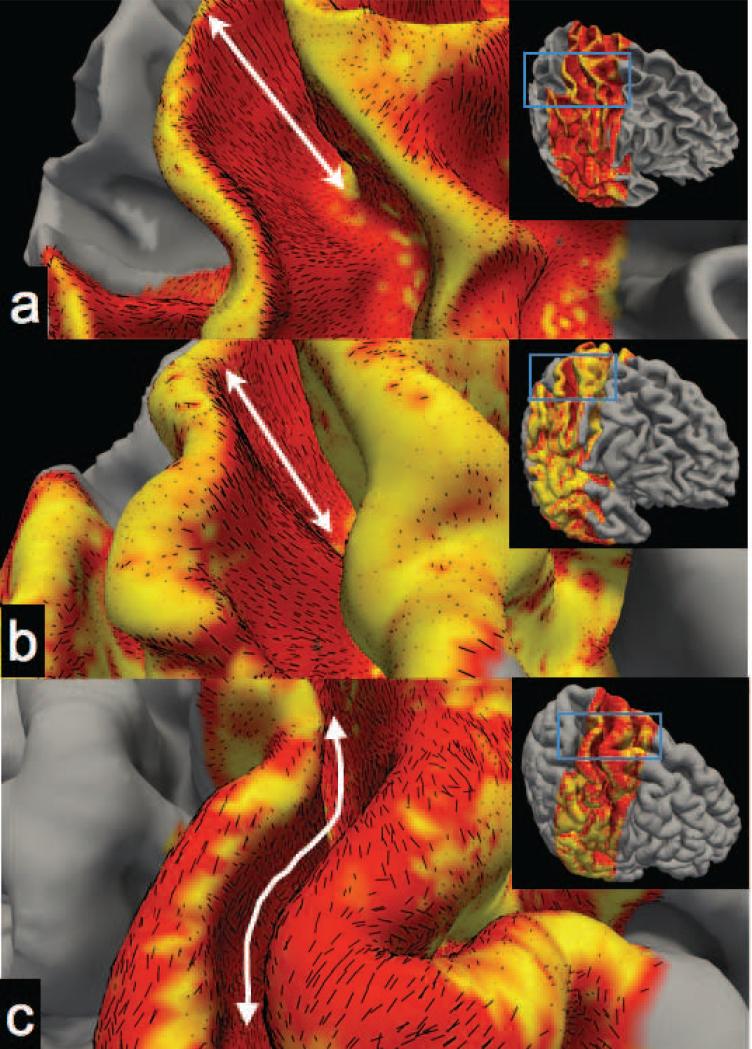

The radiality index provides a convenient visualization of the diffusion anisotropy within the cortical reference frame. For regions with radial diffusion, the orientation is uniquely described. In areas of tangential diffusion the radiality index does not distinguish the specific orientation the tangential plane. We therefore plot the tangential component of the principal eigenvector as a short line-segment on the folded cortical surface reconstruction (Fig. 7). This serves to both visualize the diffusion orientation with respect to the cortical folding pattern and the degree of spatial coherence of tangential diffusion. At the white matter surface and central depths (Fig. 7a,b) the tangential diffusion on the bank of the S1 sulcus is coherently directed along the path between the fundus and the crown. Note, at the middle cortical depth the diffusion is only tangential (red) in the S1 region of Figure 7. At the pial surface (Fig. 7c) the diffusion is tangential in extended areas but oriented differently than the deeper cortical depths. At the pial surface the tangential diffusion appears to follow the “elevation” contours of the cortical topology (i.e. along the length of the fundus and crown).

FIG. 7.

The tangential component of the primary eigenvector of the diffusion tensor (represented as yellow lines) superimposed on the radiality plots on the curved cortical surfaces for a) the interface of the white matter and the cortex, b) the middle cortical depth and c) the pial surface. Double-sided arrows highlight the dominant orientation of the vector field, i.e. between the crown and the fundus for a) and b) and along the length of the fundus and crown for c).